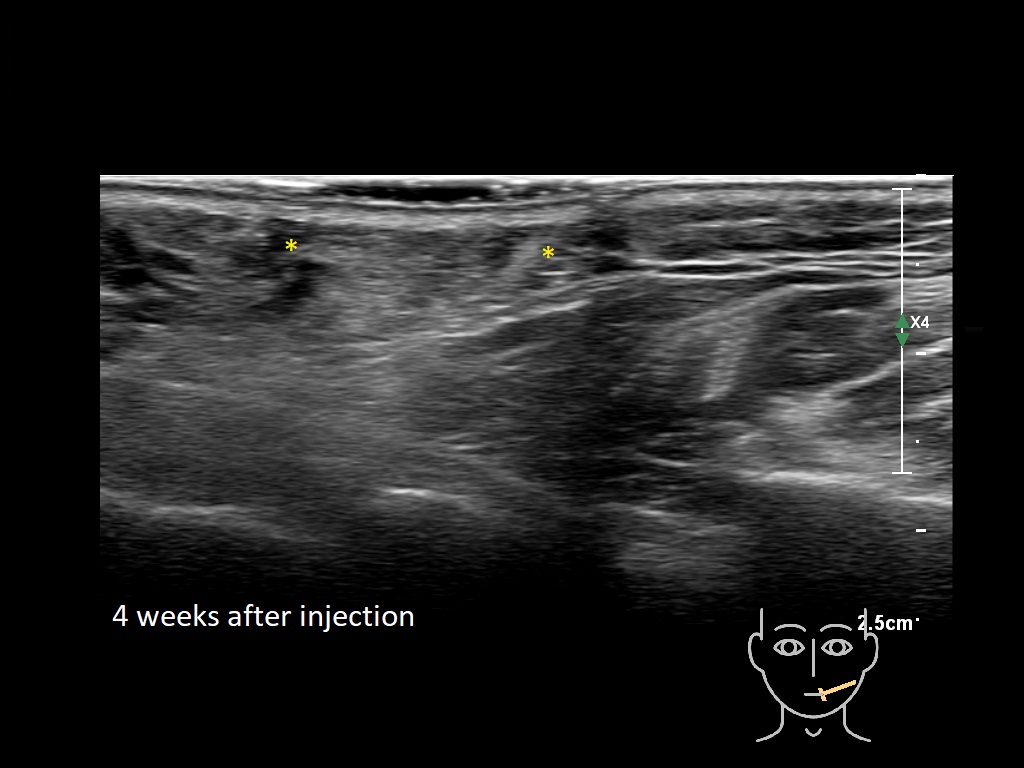

Draw in the second image below where the fillers are located. To check if your answer is correct, swipe the first image to the right.